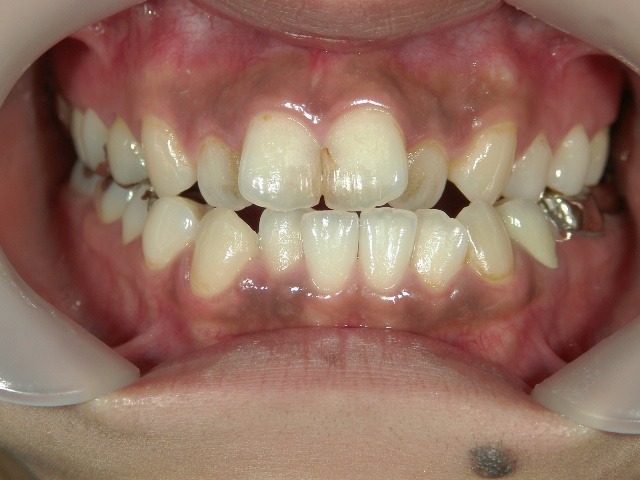

矯正歯科 治療後矯正歯科 全顎ワイヤー矯正 治療後矯正歯科(全顎ワイヤー矯正)治療後

矯正歯科 治療後

no.28_6958_治療後_右.jpgno.28_6958_治療後_正面.jpgno.28_6958_治療後_左.jpg